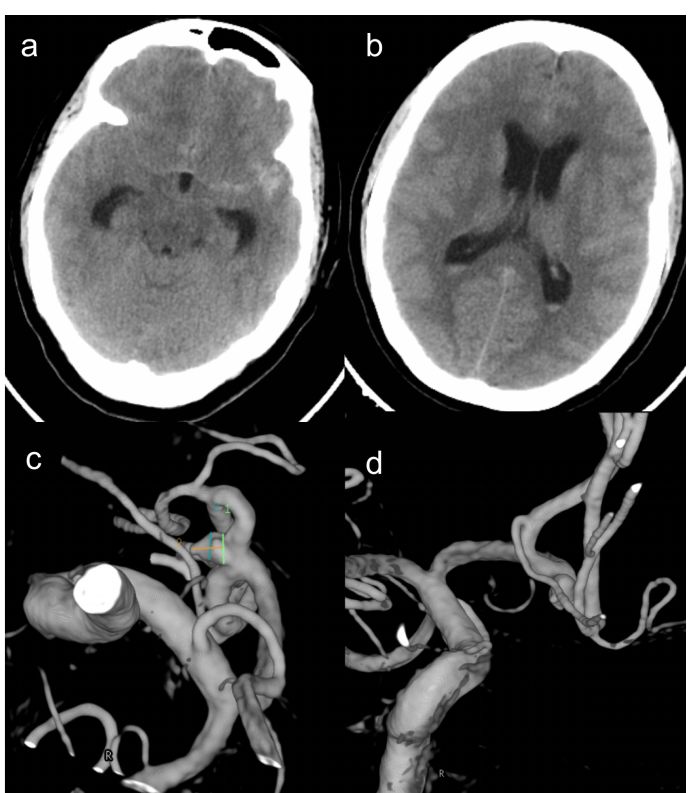

患者16小时前无明显诱因下突发头痛,呈炸裂样疼痛,伴恶心呕吐,后意识丧失,约半小时后清醒,无四肢抽搐,无口吐白沫,无大小便失禁。送至我院急诊,查头颅CT及CTA示“蛛网膜下腔出血,双侧侧脑室积血,前交通动脉瘤”。进一步行DSA检查示“右侧前交通动脉瘤”(图1)。急诊拟“前交通动脉瘤;蛛网膜下腔出血”收住入院。

图1. 术前影像学检查: a-b)头颅CT示两侧额部及左侧裂池可见高密度影,提示出血;c-d)DSA提示右侧前交通动脉瘤,瘤体大小2.8*2.8*2mm,瘤颈2.5mm